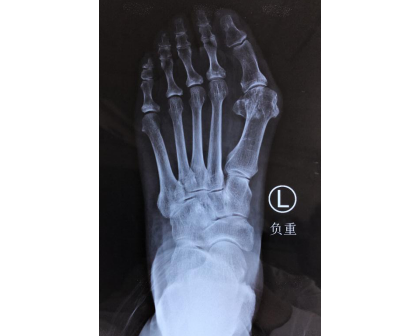

李奶奶术前(左图)术后(右图)

曹广超主任赵亮医生手术小组为李奶奶进行了增生拇囊切除,电动摆据切除跖骨头骨赘,第一跖骨做Scarf截骨,以2枚加压螺钉固定;拇内收肌松解、关节囊紧缩手术,手术很顺利,术后李奶奶被送回足踝病区进行康复。